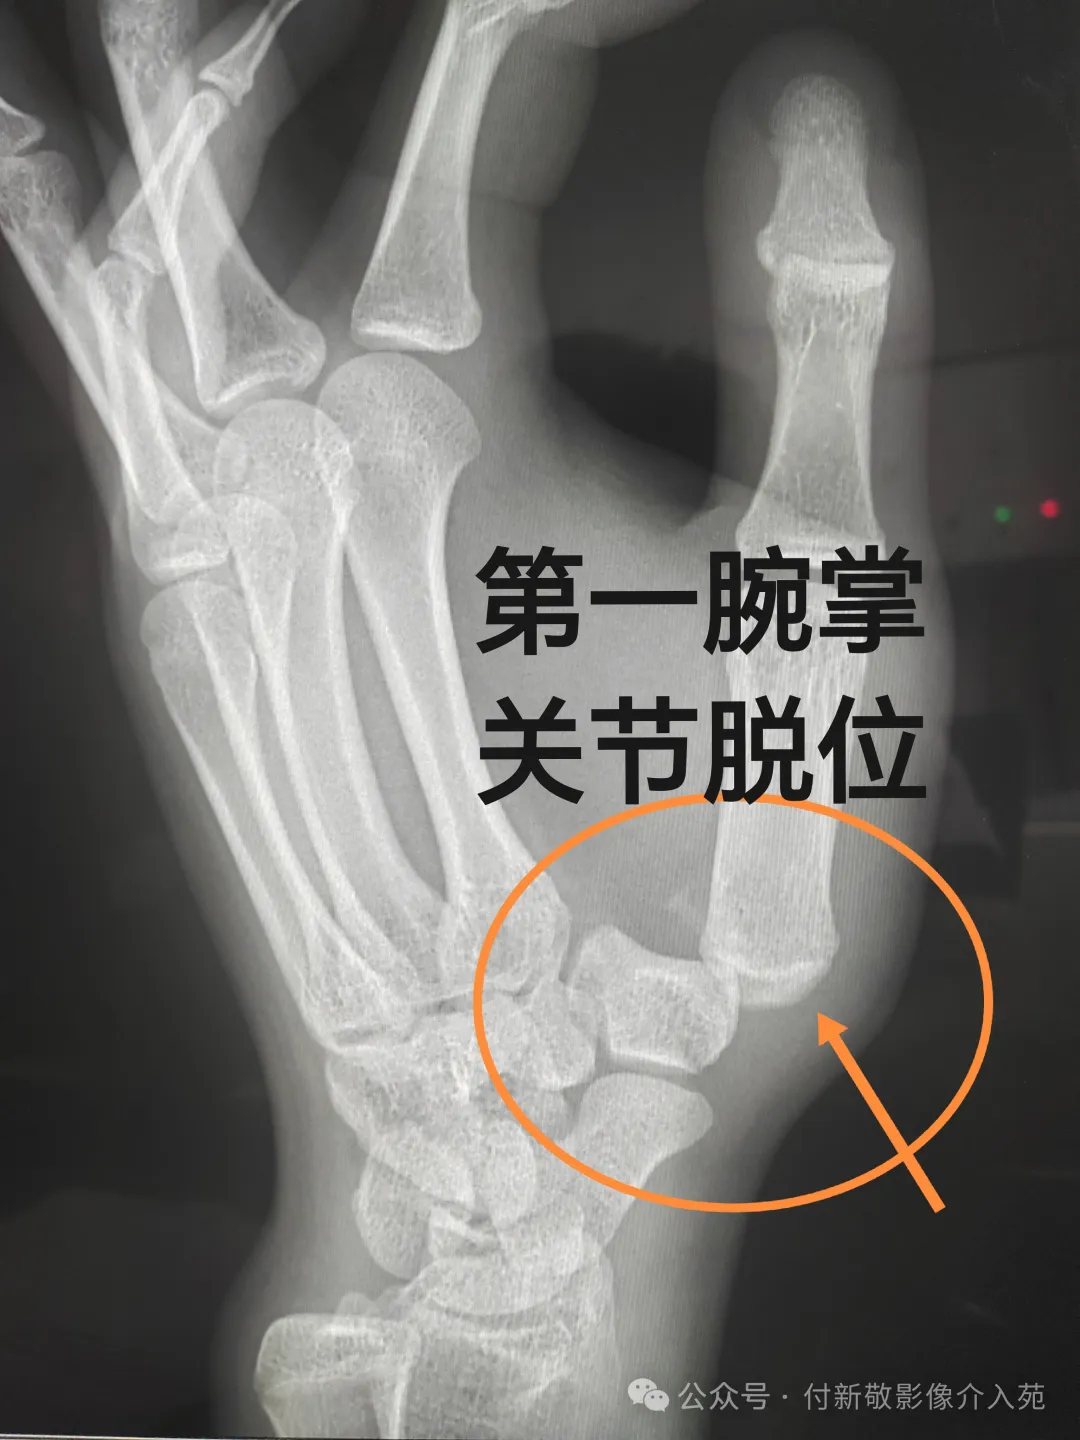

七、腕掌关节脱位

第一腕掌关节脱位:多因间接暴力导致,患者的手背部位出现肿胀、 疼痛,拇指不能活动,腕背侧压痛,第1掌骨头叩击痛,同时有松脱感,在腕背侧可触及骨端隆起畸形。严重影响工作和生活。

拇指正侧位X线检查:可以观察到第一腕掌关节对应关系异常,及关节组成骨的骨折情况。